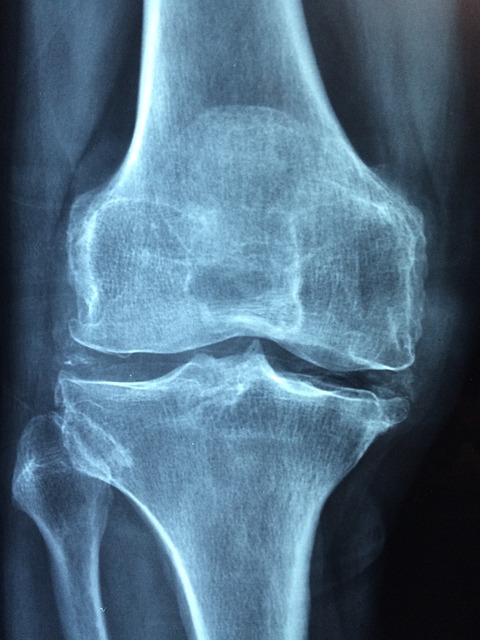

그런데 근육의 약화, 관절에 좋지 않은 자세 등 이런저런 이유로 관절에 문제가 생기면 통증이 생기고 몸을 자유롭게 움직이기 불편해집니다. 관절염은 가장 흔한 관절 질환 인데요. 연골과 같은 관절 부위에 염증이 생긴 것으로 퇴행성 관절염, 류머티즘 관절염, 통풍 등 매우 다양합니다. 관절에 통증이 생기는 것이 대표적인 증상이고, 붓거나 뻣뻣한 느낌이 들기도 해요. 관절염의 치료는 비교적 긴 시간이 걸리고, 경우에 따라 완치가 어렵고 꾸준한 관리가 필요할 수 있어요.

관절염을 예방하고 관절 건강을 지키는 가장 좋은 방법은 체중감량과 운동입니다. 체중이 줄어들수록 관절염 위험이 감소하는데요. 적정체중은 키에서 95~100을 제외한 정도라고 합니다. 관절 건강에 좋은 운동에는 관절에 부담을 주지 않는 실내 자전거 타기와 수영이 있습니다. 근력운동도 중요한데, 근육이 관절의 부담을 줄여주는 역할을 하기 때문입니다. 적당한 스트레칭을 꾸준히 해주는 것도 좋은데요. 특히 무릎은 퇴행성 관절염이 쉽게 오는 부위로 자주 풀어주는 것이 좋습니다.